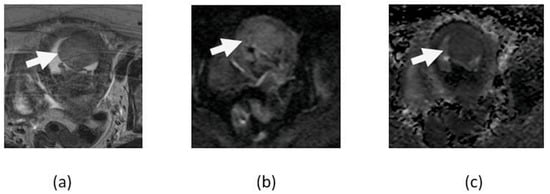

5.1. T2 Shine-Through Effect

5.2. T2 Blackout Effect

5.3. Diagnostic Pitfalls